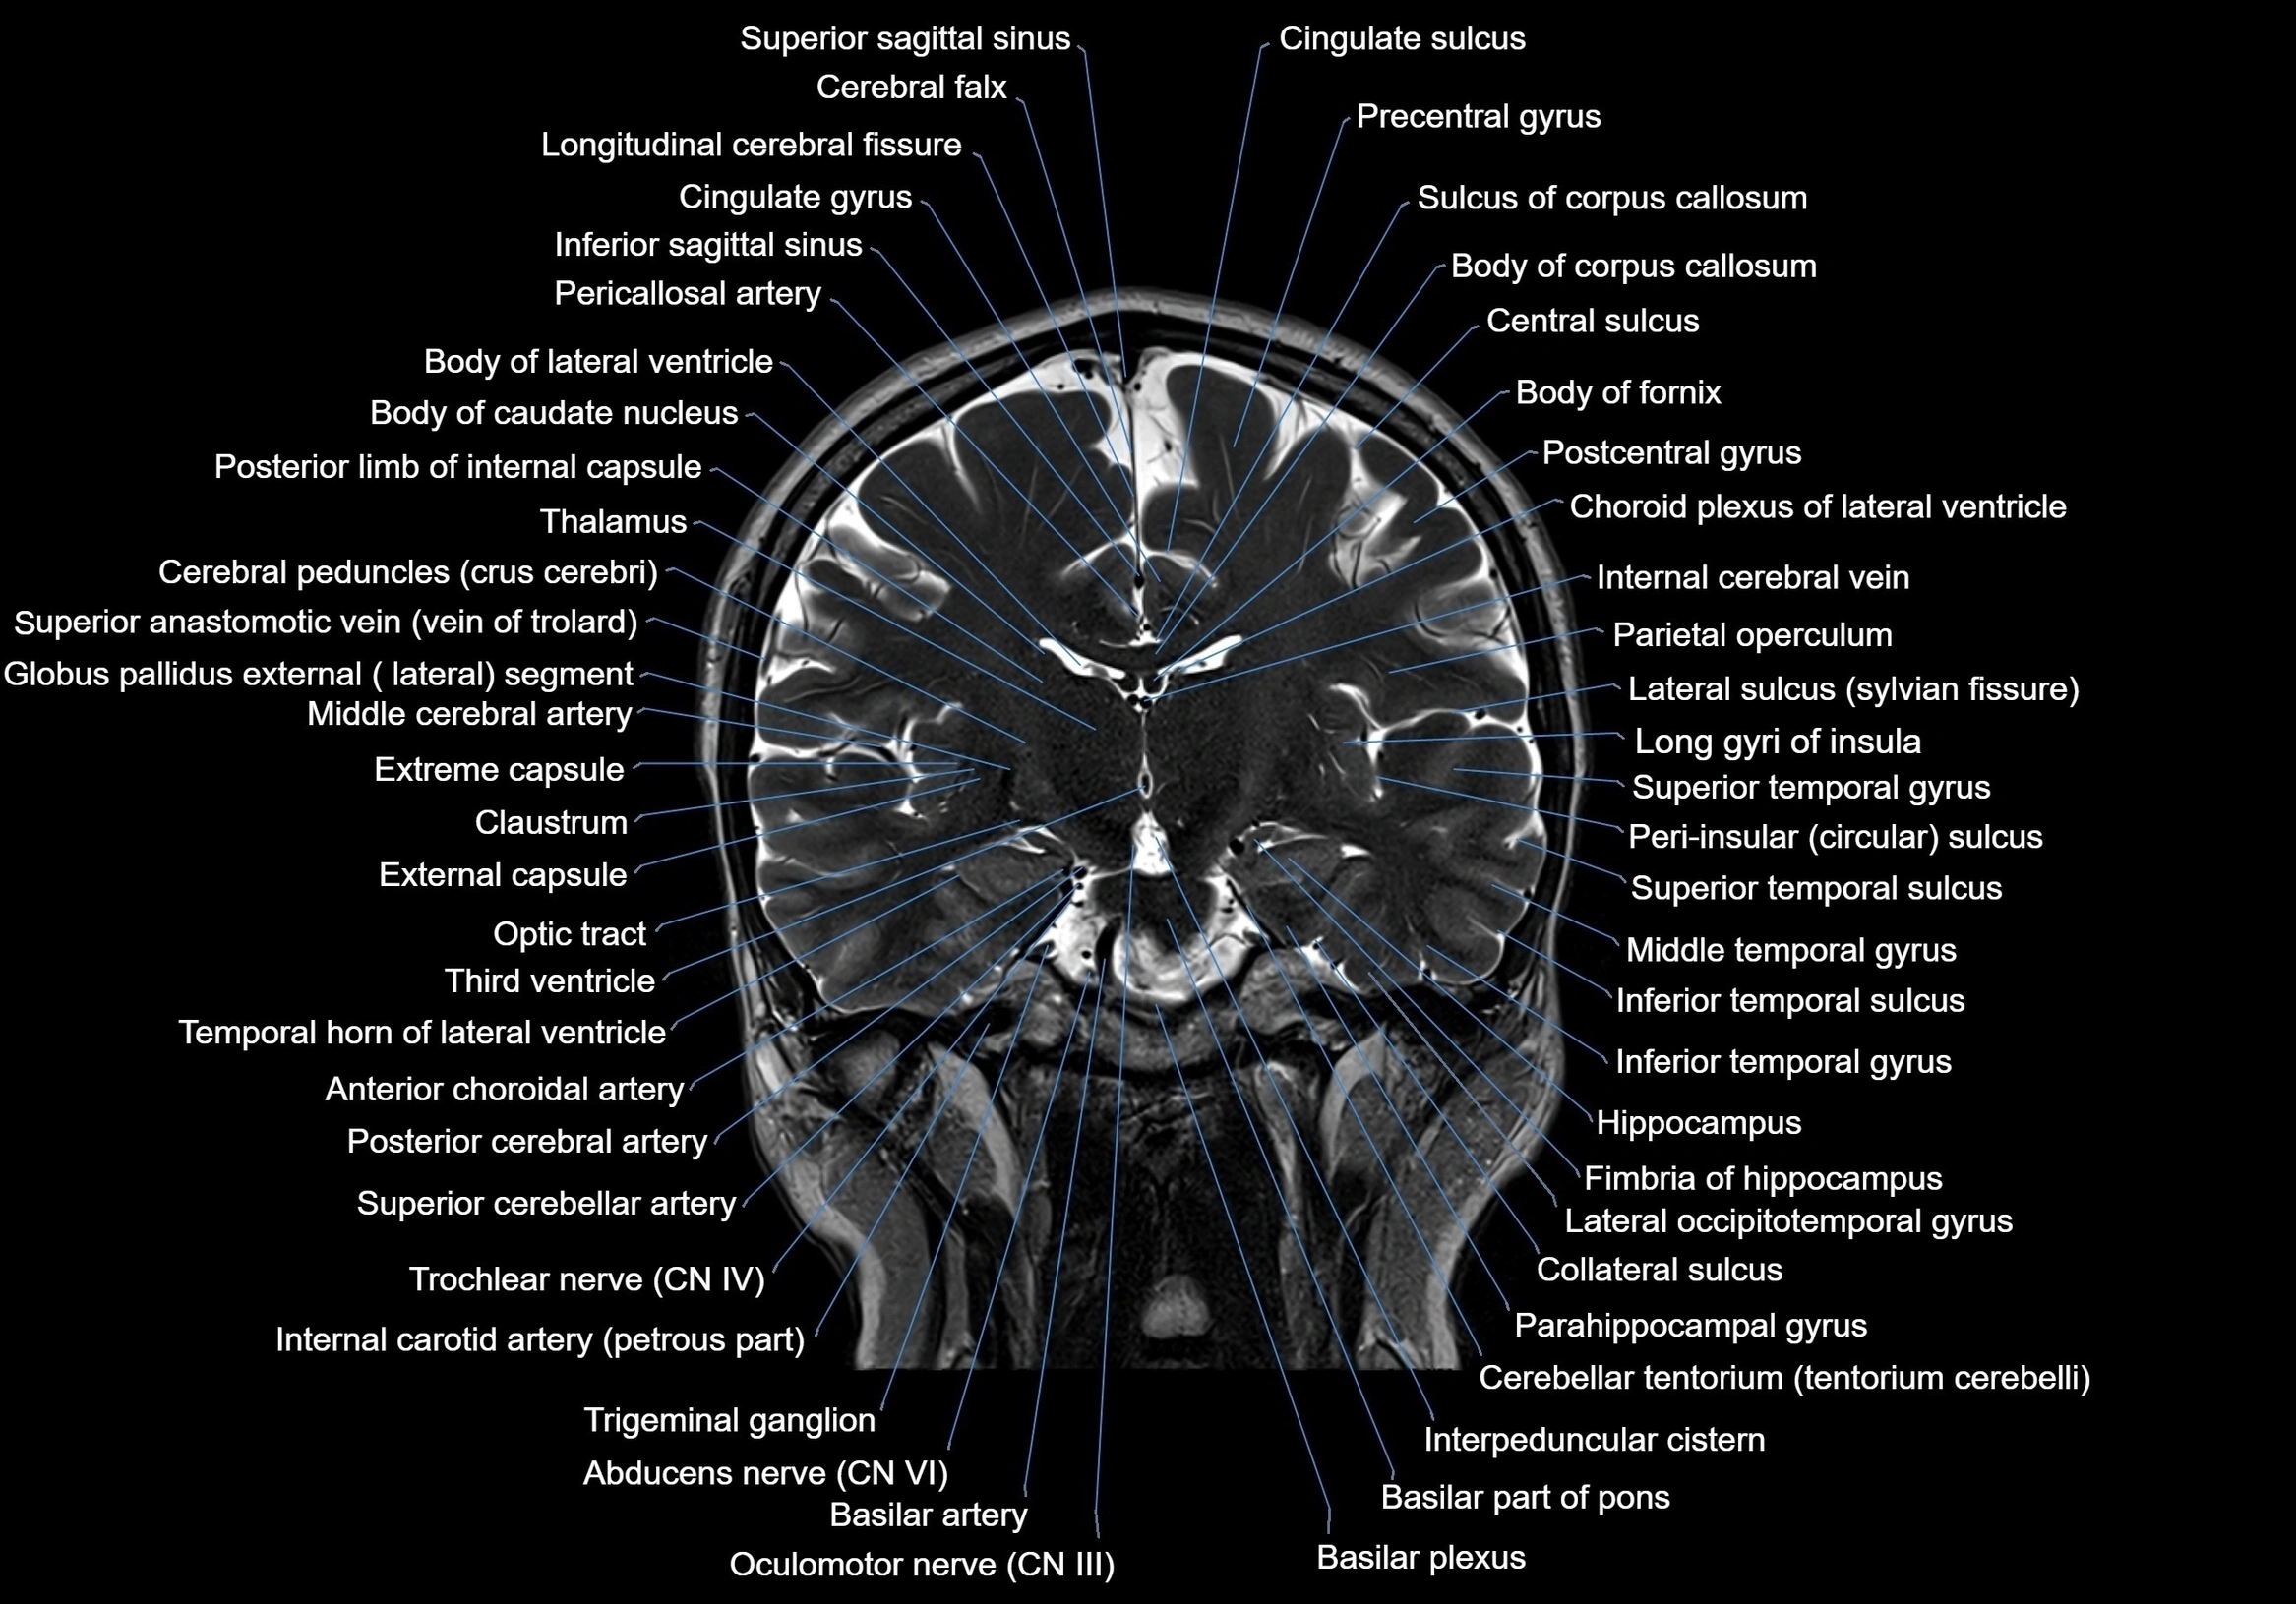

MRI images